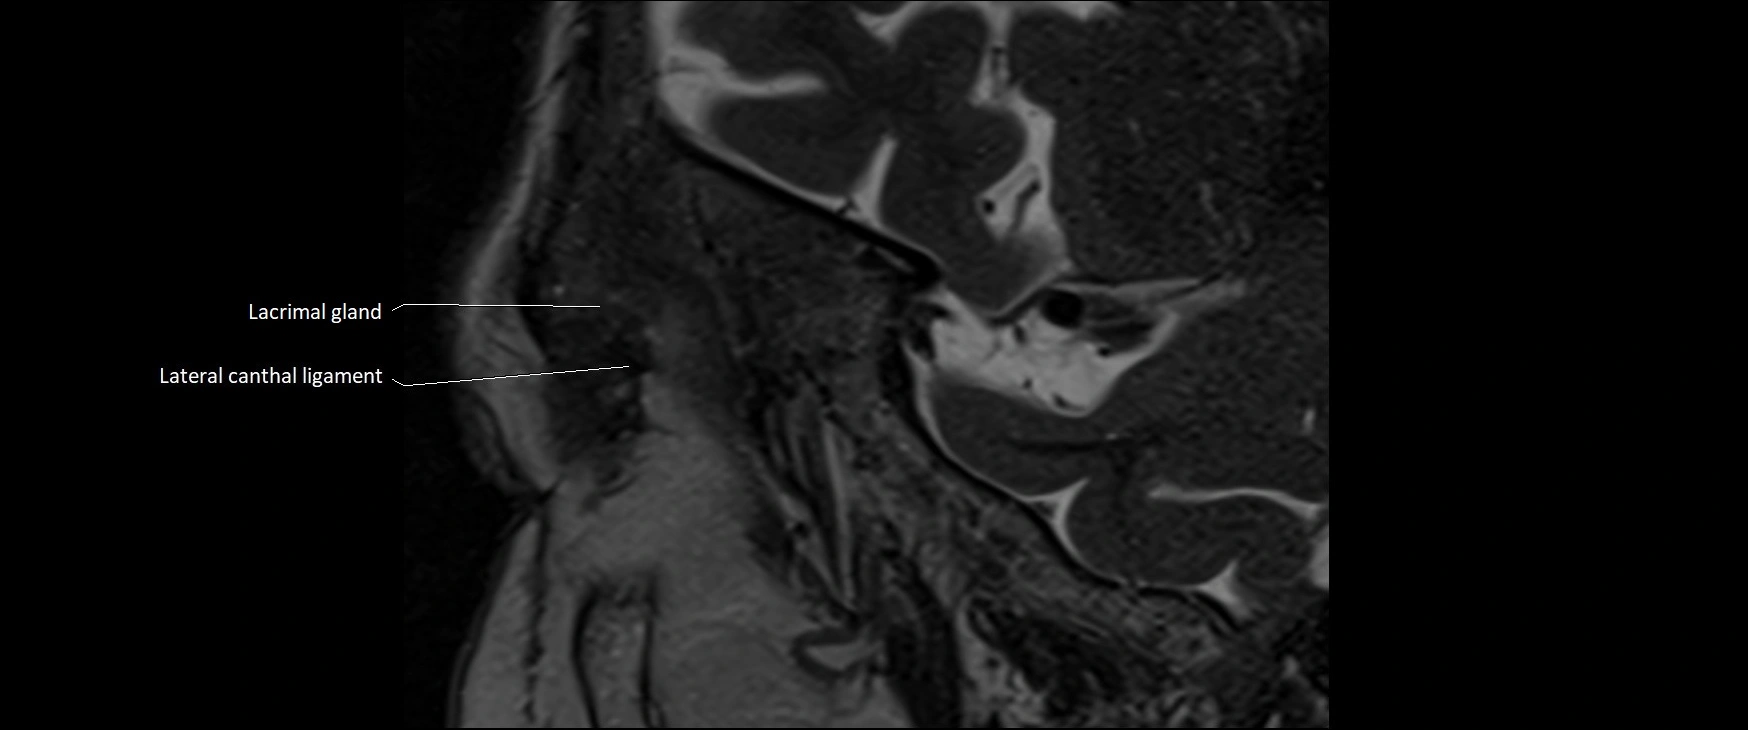

- Lacrimal gland

- Lateral canthal ligament